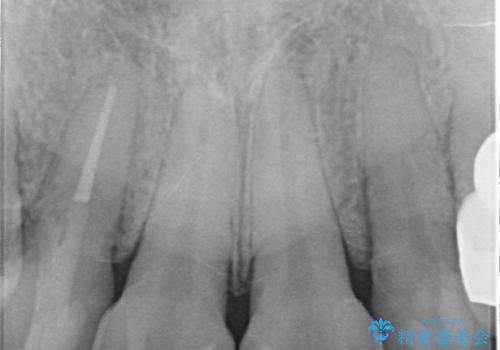

- 矯正治療後に、前歯の樹脂の詰め物のやりかえを提案していましたが、治療は当時行いませんでした。

その後3年間来院がなく、その間に前歯の虫歯の進行があり、治療を行いました。

やはり、樹脂で虫食い状になってしまうと虫歯が進行しやすくなっているためクラウンがおすすめです。

下の前歯との距離(クリアランス)が大きくは取れなかったため、ジルコニアクラウンではなくe-maxクラウンにしました。